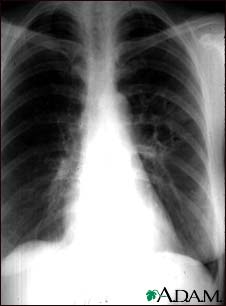

Coccidioidomycosis - chest X-ray

This chest x-ray shows the affects of a fungal infection, coccidioidomycosis. In the middle of the left lung (seen on the right side of the picture) there are multiple, thin-walled cavities (seen as light areas) with a diameter of 2 to 4 centimeters. To the side of these light areas are patchy light areas with irregular and poorly defined borders.

Other diseases that may explain these x-ray findings include lung abscesses, chronic pulmonary tuberculosis, chronic pulmonary histoplasmosis, and others.